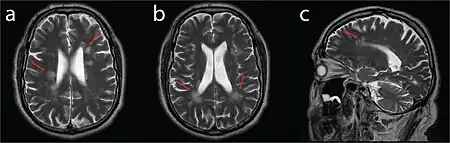

| MRI compatible with Dejerine-Sottas type spinal nerve enlargement | |

On medical imaging, the nerves of the extremities (and cranial nerves in some cases) appear enlarged due to hypertrophy of the connective interstitial tissue, giving the nerves a distinct "onion-bulb" appearance. Peripheral (and possibly cranial) nerve excitability and conduction speed are reduced.[1]